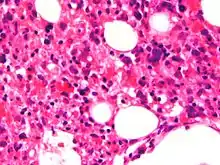

Micrograph showing red blood cells within macrophages. H&E stain.

Light microscopic image of bone marrow showing stromal macrophages containing numerous red blood cells in their cytoplasm

The blood count typically shows decreased numbers of blood cells—including a decreased number of circulating red blood cells, white blood cells, and platelets. The bone marrow may show hemophagocytosis. The liver function tests are usually elevated. A low level of the protein albumin in the blood is common.